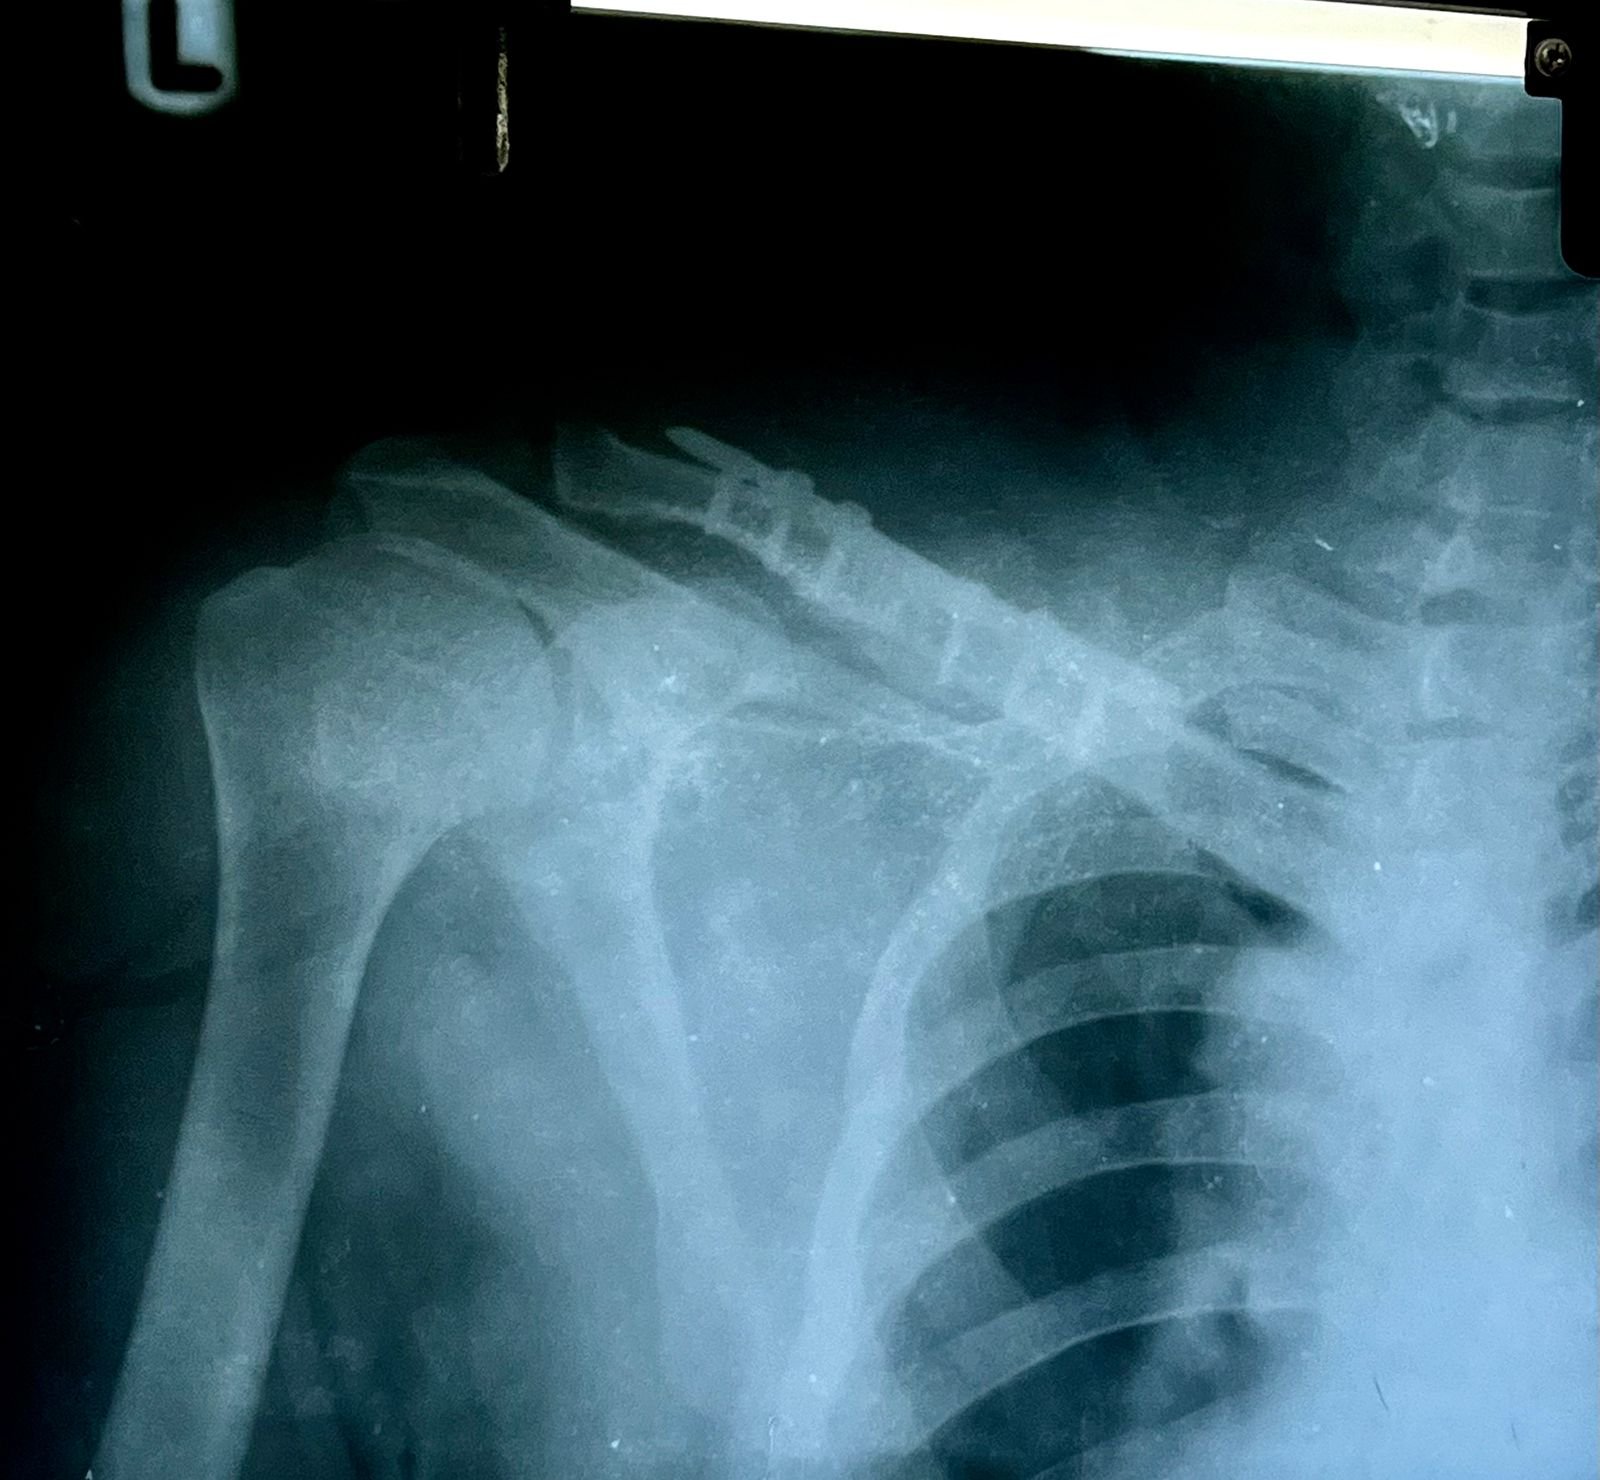

& fibula | Heal fracture pre & postop | Clavicle

fracture pre &